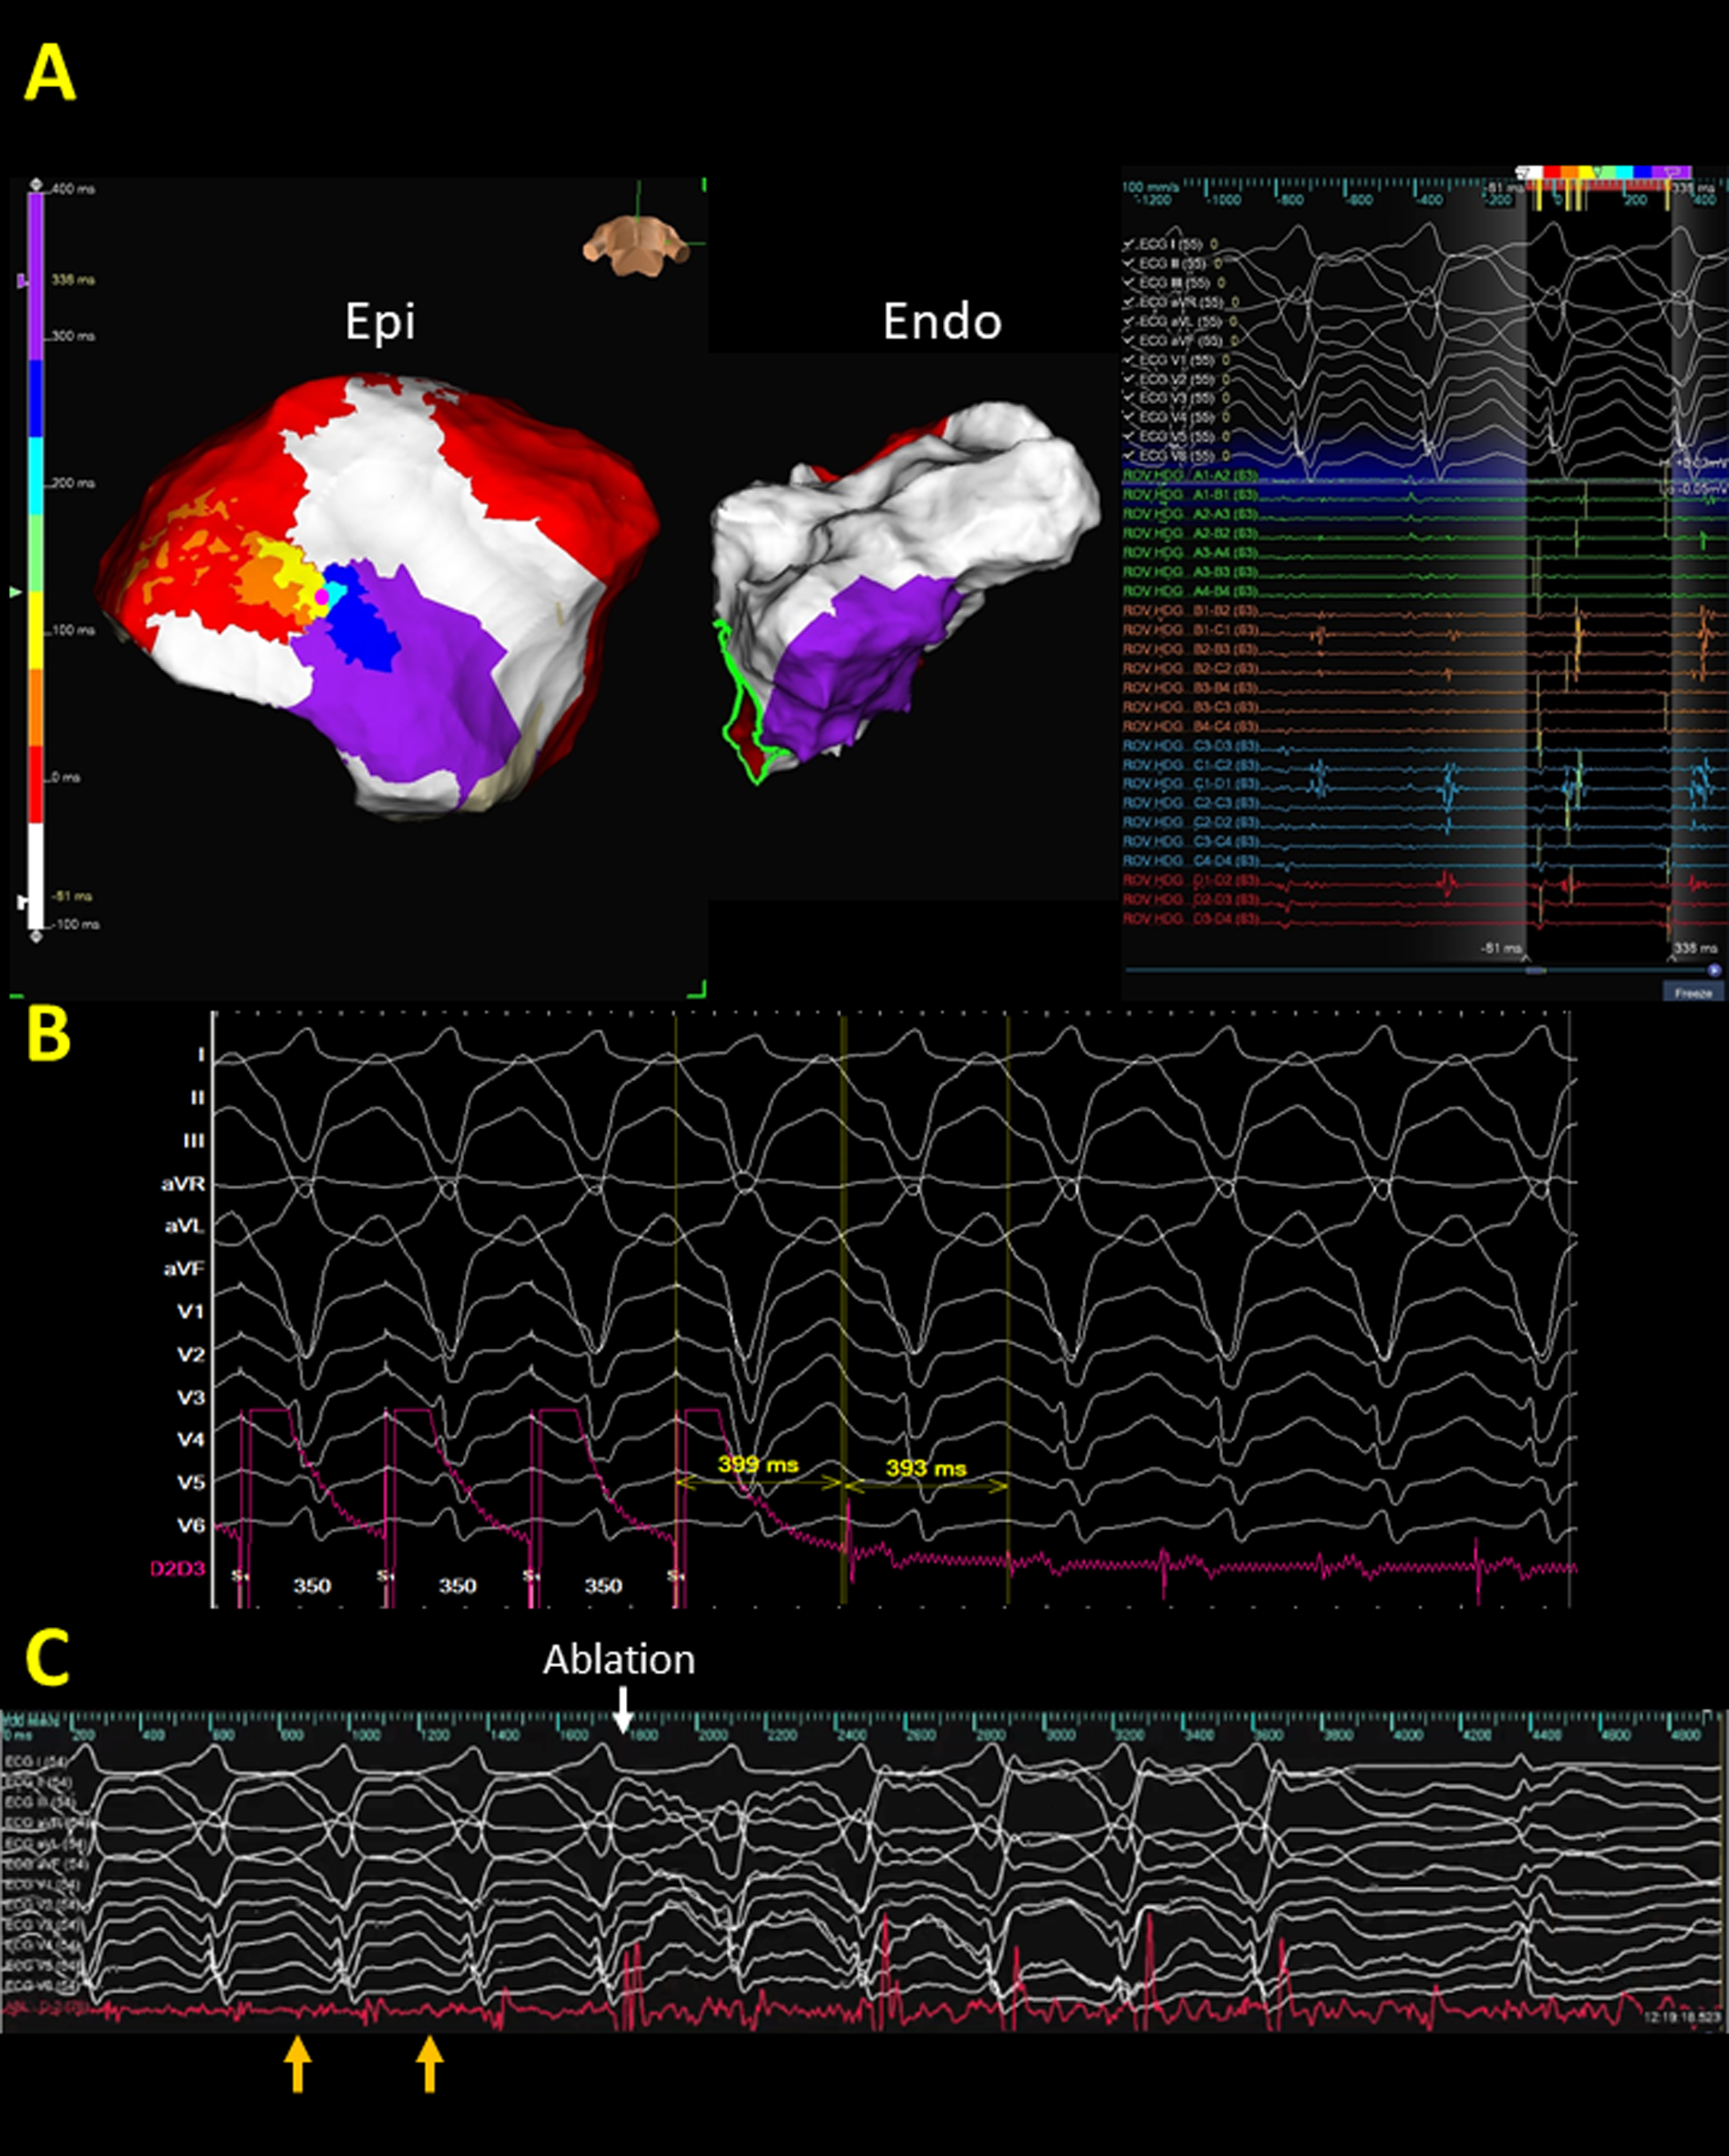

Although VF/ventricular flutter is not uncommon, macroreentrant VTs remain the most common manifestation of ventricular tachyarrhythmias in ARVC [76]. Ideally, delineation of VT circuits and targeting the critical isthmuses of VTs to terminate VTs, especially mappable VTs, would be the perfect strategy for VT ablation in ARVC. However, due to the three-dimensional VT circuits in ARVC, an incomplete epicardial circuit with an activation gap with endocardial focal centrifugal activation pattern might be encountered (Figs. 3,4). Entrainment from the earliest activation sites and the adjacent scar might provide information on the potential exit or surrogates of the reentrant circuits (Fig. 3) [77].

Fig. 3.

Fig. 3.A representative case of ventricular tachycardia (VT) isthmus localization by activation map and entrainment. (A) and (B) The VT circuit in arrhythmogenic right ventricular cardiomyopathy. Figs. 2,3 are the same case. The reentrant circuits could be recognized from the color-coded map, initiating from white, red, orange, yellow, green, blue, indigo, and violet region and the entrance to the exit of VT isthmus could be identified from the colored isochronal map from orange, yellow, green, to the blue region (Supplementary Movie 2). Notable, based on the mapping window between two onsets of QRS, the diastolic corridor is frequently located at the area with yellow, green, and blue colored region. The location of the VT isthmus was compatible with the location of the isochronal crowding region of isochronal late activation map (ILAM) (Fig. 2). Notably, an incomplete epicardial circuit with an activation gap with an endocardial focal centrifugal activation pattern is identified. (B) Concealed entrainment is achieved at the exit site of the VT isthmus. (C) Ablation at the pink dot area terminated the VT within 2 s. Diastolic potentials (orange arrows) were recorded by the distal electrode of the ablation catheter.

Fig. 4.

Fig. 4.A representative case demonstrates the correlation between deceleration zone and ventricular tachycardia (VT) isthmus. (A) isochronal late activation map (ILAM) of epicardial substrates. Compared to the bipolar voltage map (Fig. 2), ILAM provided informative and functional properties of the two deceleration zones within the RV outflow epicardium. (B) VT activation demonstrated that the VT circuit is compatible with the superior isochronal crowding region. Notably, an incomplete epicardial circuit with an activation gap is recorded, and both far-field and near-field potentials are recorded by high-density mapping.